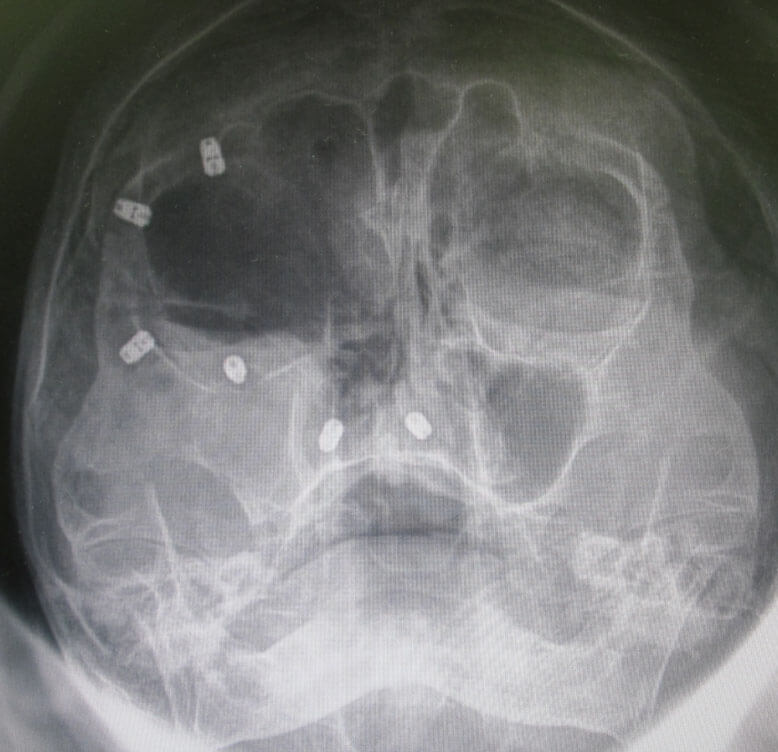

In cases where complex reconstructive surgery cannot match the functional and aesthetic outcomes of an implant-retained prosthetic facial prosthesis, the placement of small, hidden titanium screws anchoring to the facial skeleton bone is ideal. For example, an elderly woman who lost her nose and right eye to skin cancer had six titanium bone implants placed to firmly hold a facial prosthesis (see next image).